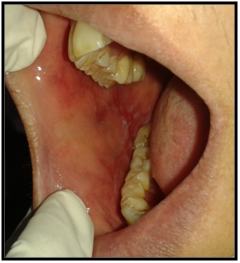

On intraoral examination, diffuse lesions in the form of erythematous areas were seen interspersed within white keratotic areas present all over the facial aspect of gingiva (Figure 2) and more posteriorly on the buccal mucosae bilaterally (Figure 3). Left buccal mucosa showed a white erythematous patch measuring approximately 2x2.5cms extending anteroposteriorly from the area adjacent to mandibular first molar to the retro molar pad area and superior inferiorly from the line of occlusion to the upper and lower lingual vestibule. White radiating striae (wickhamstriae) were present with an interspersed erythematous patch. Right buccal mucosa showed a more extensive lesion measuring approximately 2.5x3cms extending anteroposteriorly from the region adjacent to mandibular canine to the retromolar pad area and superioinferiorly from the upper gingiva buccal sulcus to the lower gingivobuccal sulcus and the alveolar mucosa. Borders of the lesion appear irregular and ill defined. On palpation, the lesions appeared to be tender. The surface of the lesions were rough and non scrapable with no induration noted.

Figure 3 The lesion on the facial gingiva.